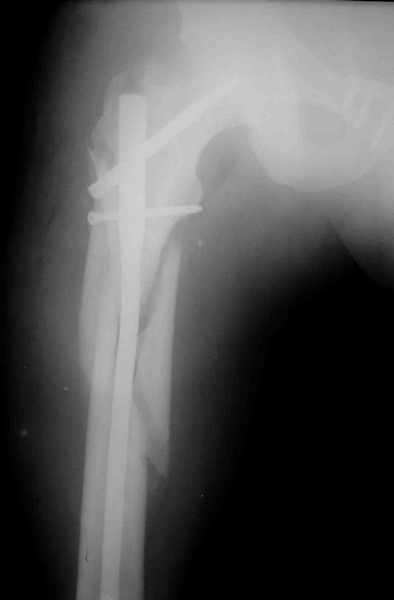

ПЕРЕСМАТРИВАЛ РАЗНЫЕ СНИМКИ И НАШЕЛ НА ЭТУ ТЕМУ ФОРУМА СНИМОК. БОЛЬНОЙ БЫЛ ПРООПЕРИРОВАН НА ПРАВОЕ БЕДРО ПОСЛЕ ЧЕГО СДЕЛАН ТАЗ В ЦЕЛОМ. ВОТ ЧТО НАШЛОСЬ.

КАКОЕ ВАШЕ МНЕНИЕ О ТАКТИКЕ.

ДУМАЮ ПРОШЛО ОКОЛО 10 ДНЕЙ.